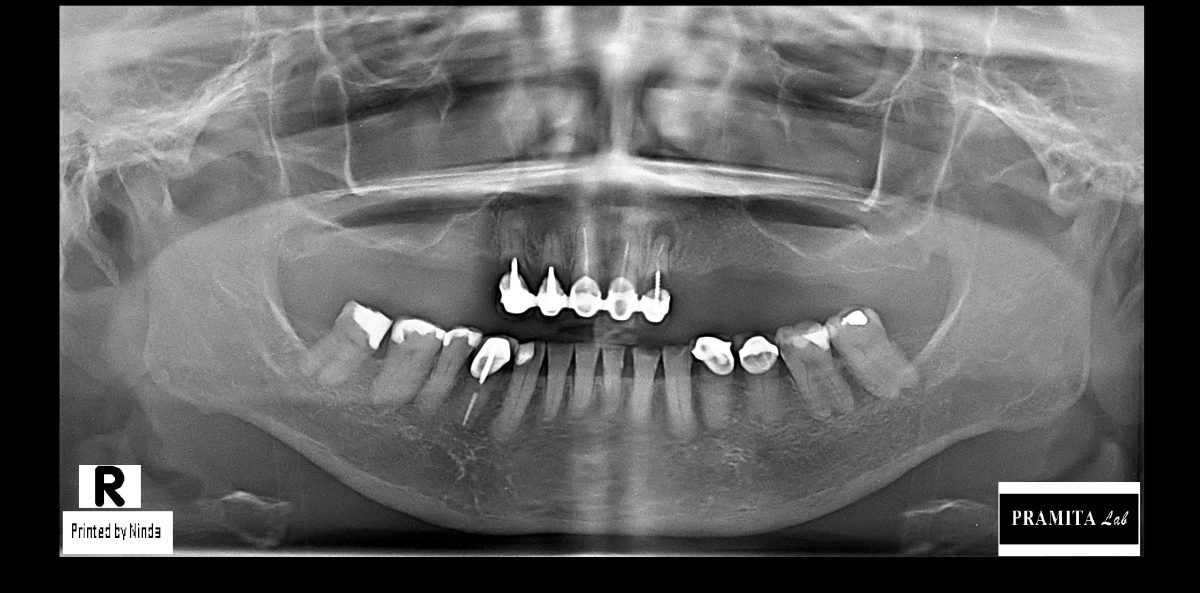

All-on-X dental implants are a full-arch restoration solution designed for patients with multiple missing, damaged, or failing teeth. The treatment uses four, five, or six dental implants to support a fixed full-arch prosthesis, restoring both function and aesthetics.

The number of implants required depends on bone condition, bite forces, and overall treatment planning.

The timeline depends on your case and bone condition.

Some implant cases may require multiple visits over several months, while others can be completed faster using immediate-loading techniques or temporary restorations.

Before your trip, our dentists can review your X-rays or scans and provide a personalized treatment timeline.

Yes. Many international patients send us:

* dental X-rays

* CT scans

* intraoral photos

* previous treatment records

before traveling to Bali.

This helps our dentists better understand your condition and prepare a preliminary treatment plan before your arrival.